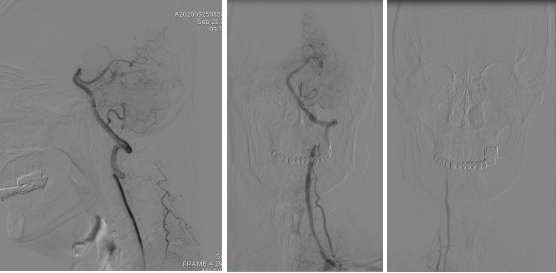

全脑血管造影:右侧大脑中动脉M1分叉处动脉瘤,瘤体3.3 mm*4.1 mm,瘤颈2.7 mm。前交通动脉瘤栓塞完全。

全麻满意后,常规消毒铺巾,采用改良 Seldinger技术穿刺右侧股动脉成功,置入6F动脉鞘。黑泥鳅导丝带领5F单弯导管行脑动脉造影,右侧颈内动脉造影见:右侧大脑中动脉M1分叉处动脉瘤,瘤体3.3 mm*4.1 mm,瘤颈2.7 mm。前交通动脉瘤栓塞完全。

经右侧股动脉鞘,黑泥鳅导丝带领导引导管(Codman 6F Envoy DA)到达右侧颈内动脉岩段,微导丝(Synchro--14 0.014 in*200 cm)带领支架微导管(Excelsior SL--10)到达右侧大脑中动脉M2段,退出微导丝。微导丝带领弹簧圈微导管(Echelon10)到达右侧M1远端分叉处动脉瘤内,退出微导丝。经弹簧圈微导管填入弹簧圈(Codman 3 mm*4 cm)经支架微导管输送支架(Neuroform Atlas 3.0 mm*15 mm)并释放在M2段至M段中部,完全覆盖动脉瘤颈。继续经弹簧圈微导管依次填入弹簧圈数枚,间断造影确保右侧大脑中动脉及远端血流通畅。右侧颈内动脉造影确认:动脉瘤致密填塞,载瘤动脉通畅,手术结束。有侧股动脉穿刺处用血管封堵器封堵,并压迫器持续压迫。术后患者麻醉清醒,拔除气管插管,呼唤应答,对答切题,言语清楚,四肢肌力肌张力正常。安返病房。